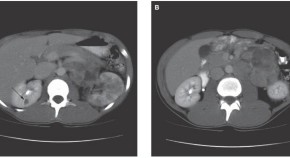

• Papillary type 2 renal cell carcinoma (RCC) is part of the hereditary leiomyomatosis and renal cell carcinoma syndrome that is caused by a mutation in the fumarate hydratase (FH) gene. In this article, the authors present a tragic case of a young man who was diagnosed with papillary type 2 RCC and was managed with radical nephrectomy, immunotherapy, chemotherapy and surgical debulking. The article discusses the treatment and management of patients with renal manifestations of FH heterozygosity that are the most serious aspects of the syndrome, and underlines the need for genetic evaluation of patients and members of their families.